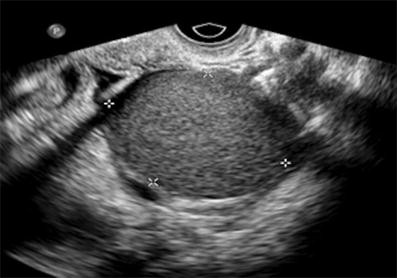

Homogeneous low-level echoes described as “ground glass.”

What is an endometrioma?